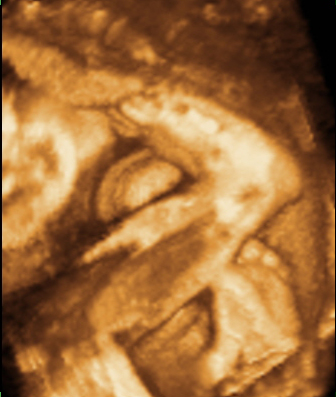

Kexi: hidd el én is nagyon parázok, de úgy vagyok vele mint Annus, elhessegetem a rossz gondolatokat. Megpróbálom élvezni a terhességet, mert ez olyan szép dolog, de ha állandóan aggódok, akkor nem lehet. Én úgy vagyok vele, hogy mindent megteszek hogy minden simán menjen. Szedem a gyógyszereket, nagyon sokat pihizek, semmi megeröltetés és a doki is azt mondta hogy ez minden amit tehetek. Ja és a nyálkahártyám a doki szerint szép vastag. Kicsi Csiga pedig kapaszkodik ezerrel, mert megbeszéltem vele

Jövő hét szerdán doki, már annyira váááároooom

remélem már úgy dübörög a kis szíve mint egy hadsereg